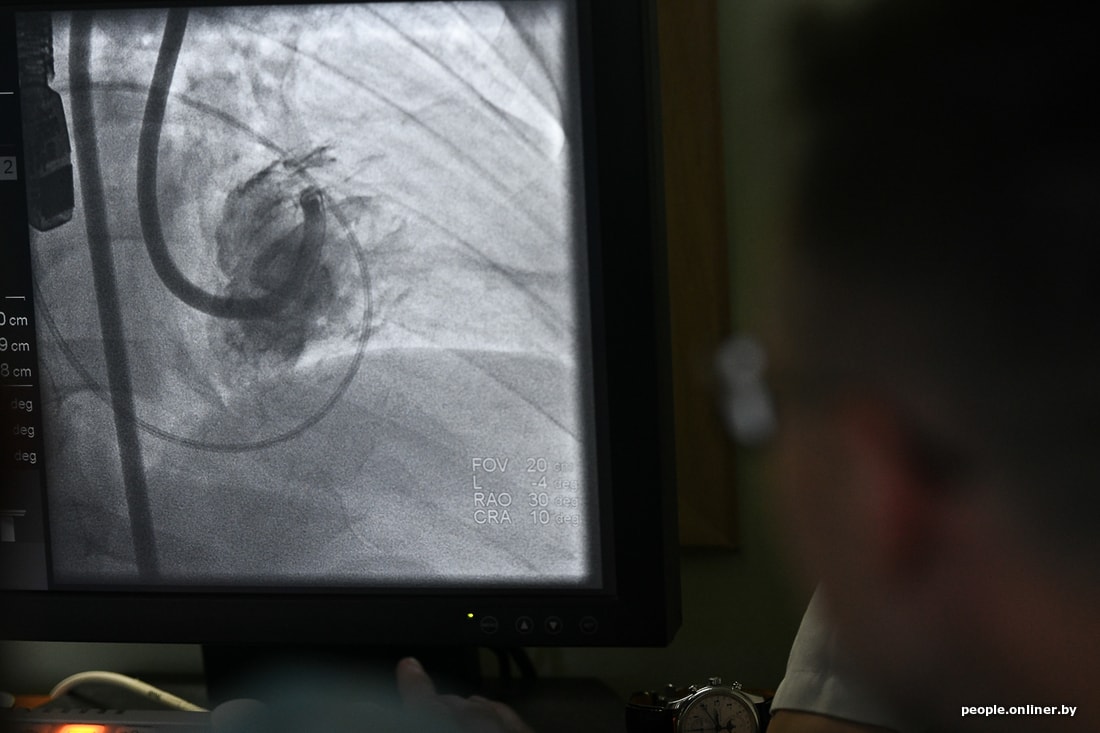

Это не просто прогрессивная методика, она очень интересная, если можно сказать, остроумная. Калифорнийские специалисты создали устройство, которое позволяет уменьшить раздутый желудочек сердца изнутри. Устройство заводится внутрь полости сердца, и в стенку сердца изнутри вводятся якоря, соединенные ниткой, шнуром. Стягиваются. Тем самым раздутый желудочек уменьшается, принимает свой оптимальный размер, начинает лучше работать. Потому что чем желудочек больше, тем сложнее ему сокращаться по физическим законам. Я ввожу катетеры через бедренную артерию под контролем рентгена и ультразвука. Техника заключается в том, чтобы через артерии довести устройство до сердца и расположить внутри именно там, где нужно. Тут уже работает команда: и кардиологи, и ультразвуковые диагносты, и мы, рентгеноэндоваскулярные хирурги.